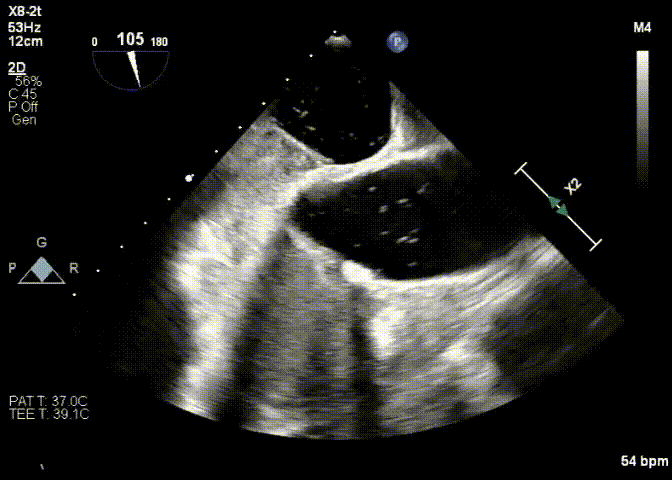

Imagem da Semana

Dessa vez trouxemos uma imagem de uma fonte pouco usual: a prova de título de especialista em cardiologia 2024 (TEC 2024). Esse belo forame oval patente (FOP) fez parte da questão 58, que questionava aspectos do manejo do paciente com FOP e AVC.

Sem querer nos gabar, mas já nos gabando rs, o leitor da DozeNews “matava” essa questão de cara por 2 motivos: trouxemos uma imagem muito semelhante na edição da DozeNews do dia 30/09 e temos uma bela DozeNews Prime que discute amplamente o tema.

Vai prestar o TEC em 2025? Já sabe né? 😉